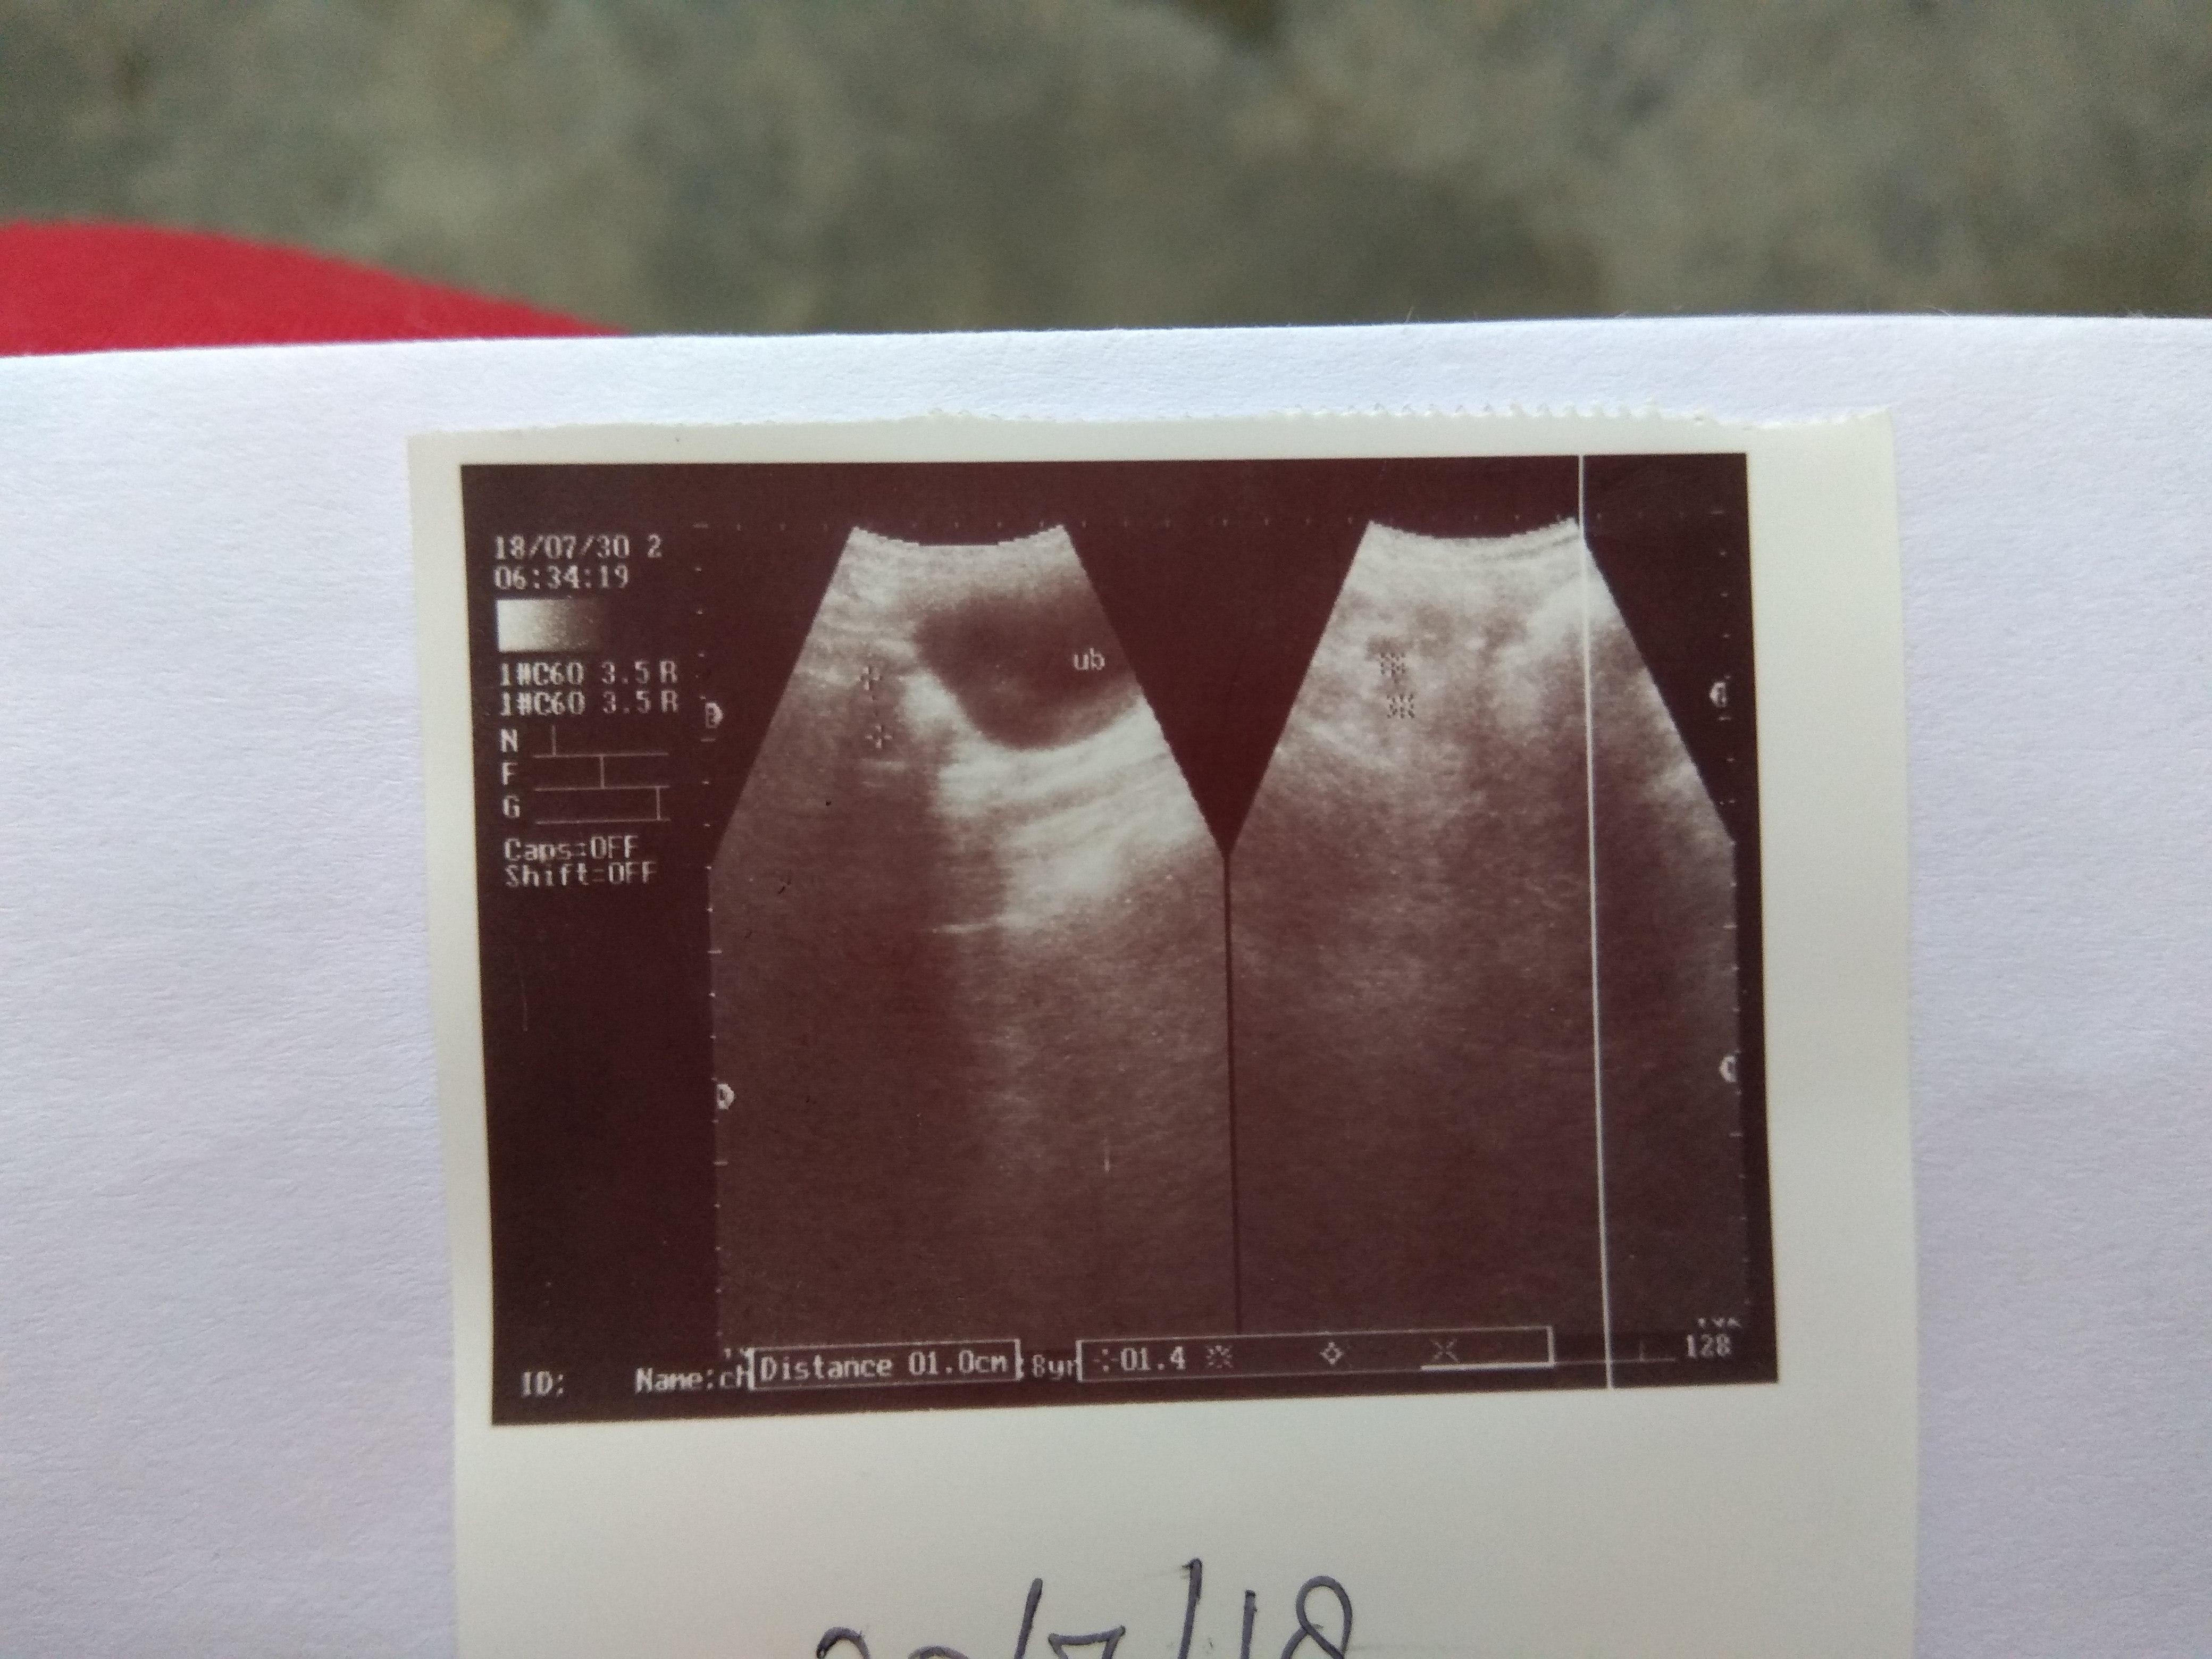

My female dog was having discharge from her vulva then vet gave med for 10 days then told ultrasound then 2nd vet who did ultrasound said vaginitis only n gave vaginal pessary n did ultrasound after a week again n said infection there,surgery is required from ultrasound report.bt I feel Dr is very money minded(from his reviews,attitude).she initially was sometimes off food n sleepy bt now seems normal,active,eating okay.plz see ultrasound pics n tell uterus is visible? discharge is still there.

It's a little difficult to see for certain in the picture, but I do see a fluid filled structure in the photo near the urinary bladder that certainly could be the uterus. In your final picture the discharge on the ground does not look what I would typically expect from vaginitis. You may want to get a third opinion from a veterinarian if you're concerned about going forward with surgery. If it is a uterine infection it is unlikely to clear with antibiotics alone and even if it does the infection returns with the next heat cycle, so I typically recommend surgery whenever I am concerned about a pyometra.

I would recommend to have surgery performed if it is the best recommended option. I would say that there is fluid in the uterus and increased shadowing, it is just a picture so difficult to fully comment. I know it is a surgery but it is very common for dogs to suffer with pyrometers as they get old, so it would prevent her anyway from getting it, hope this helps